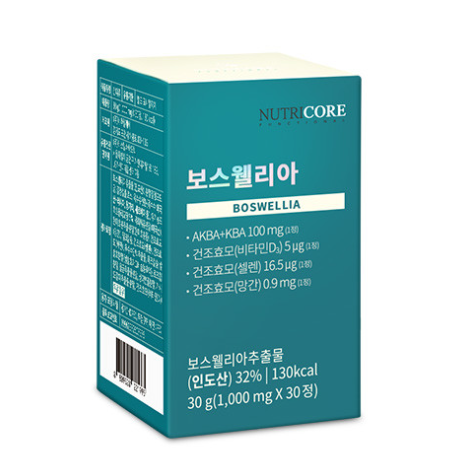

뉴트리코어 보스웰리아는 핵심성분인 AKBA+KBA가 1정 당 무려 100mg가 함유된 프리미엄 제품으로 관절 건강에 도움을 주는 건강기능식품입니다. 보스웰리아는 미국 국립보건원에서도 주목한 글로벌 건강 소재이기도 합니다.

또 관절 건강에 도움을 주는 부재료인 건조효모인 비타민D3, 셀렌, 망간이 함유되어 있는데요. 비타민D3는 칼슘 농도와 골밀도를 유지시켜 뼈 건강에 도움을 주는 성분이며, 망간은 항산화와 염증을 줄이는 데에 도움을 주는 성분입니다.

뉴트리코어 보스웰리아 가격은 뉴트리코어 공식 홈페이지 기준 1개월분에 39,000원입니다. 4개 구매 시에는 1개가 추가 증정되는 이벤트를 진행하고 있으니 행사내용을 확인해 보시길 바랍니다.